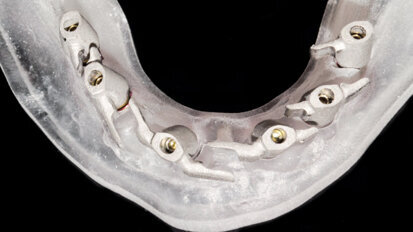

Dělený třmen jako výztuž provizorní náhrady

Realizace rekonstrukce celého zubního oblouku pomocí náhrady nesené implantáty je po všech stránkách náročným typem ošetření a vyžaduje ...

Fixní rekonstrukce celého oblouku nesená implantáty: Využití „full-template guidance technique"“

Fixní rekonstrukce celého oblouku nesené implantáty vyžadují správnou diagnostiku a plánování léčby. Jen tak je možno zhodnotit stávající ...